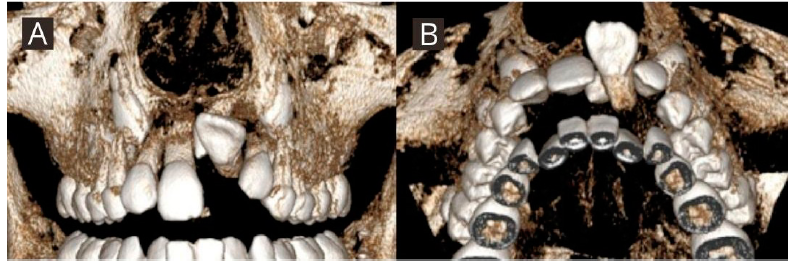

Paciente de género femenino de 9 años de edad, sin antecedentes mórbidos, perfil convexo, clase II esqueletal. En el análisis intraoral se observó dentición mixta primera fase, ausencia del diente 21, neutroclusión molar bilateral, discrepancia óseo-dentoalveolar moderada superior y severa inferior, relación transversal favorable, línea media dentaria superior desviada un milímetro a la izquierda respecto a la línea facial y la línea media dentaria inferior centrada con la línea media facial (Figura 1. A-D). En el análisis con CBCT, realizado con el software Nemotec® se observó el diente 21 en evolución intraósea en una posición alta, horizontal y paralelo al plano oclusal, con formación radicular incompleta, con una distancia de 26.39 milímetros al borde incisal del incisivo central contralateral, y asociado a este se encontró un diente supernumerario en posición alta en relación con el piso de fosas nasales, de forma coronaria cónica ubicado hacia palatino (Figura 2. A-B). En la primera fase de tratamiento, se inició por la desinclusión del diente supernumerario y luego se abordó el diente 21 mediante una exposición quirúrgica cerrada realizada por un cirujano maxilofacial, en el mismo acto quirúrgico se instaló un botón vestibular y uno palatino de refuerzo con ligadura de acero inoxidable de 0.9 Ferderhard (FH) para la tracción. Se realizó instalación de biteblock céntrico, el cual consistió en un dispositivo interoclusal cementado confeccionado en articulador digital para mantener la funcionalidad masticatoria y evitar contactos prematuros, y que tiene un botón central para otorgar rigidez que fue activado ¼ de vuelta a diario por 12 días. Desde este botón se confeccionó un brazo de tracción en alambre de acero inoxidable de calibre 0.8 FH, realizando la activación de la tracción 15 días posterior a la cirugía cada cuatro semanas, dejando la encía del reborde marginal levemente isquémica con una fuerza de aproximadamente 50 gramos (Medidor de tensión VTSYIQI model ATG-500-2 ®) (Figura 3. A-B).

Figura 2 Representación tridimensional de posición inicial de diente 21 evaluado en CBCT. A. Vista frontal. B. Vista axial.